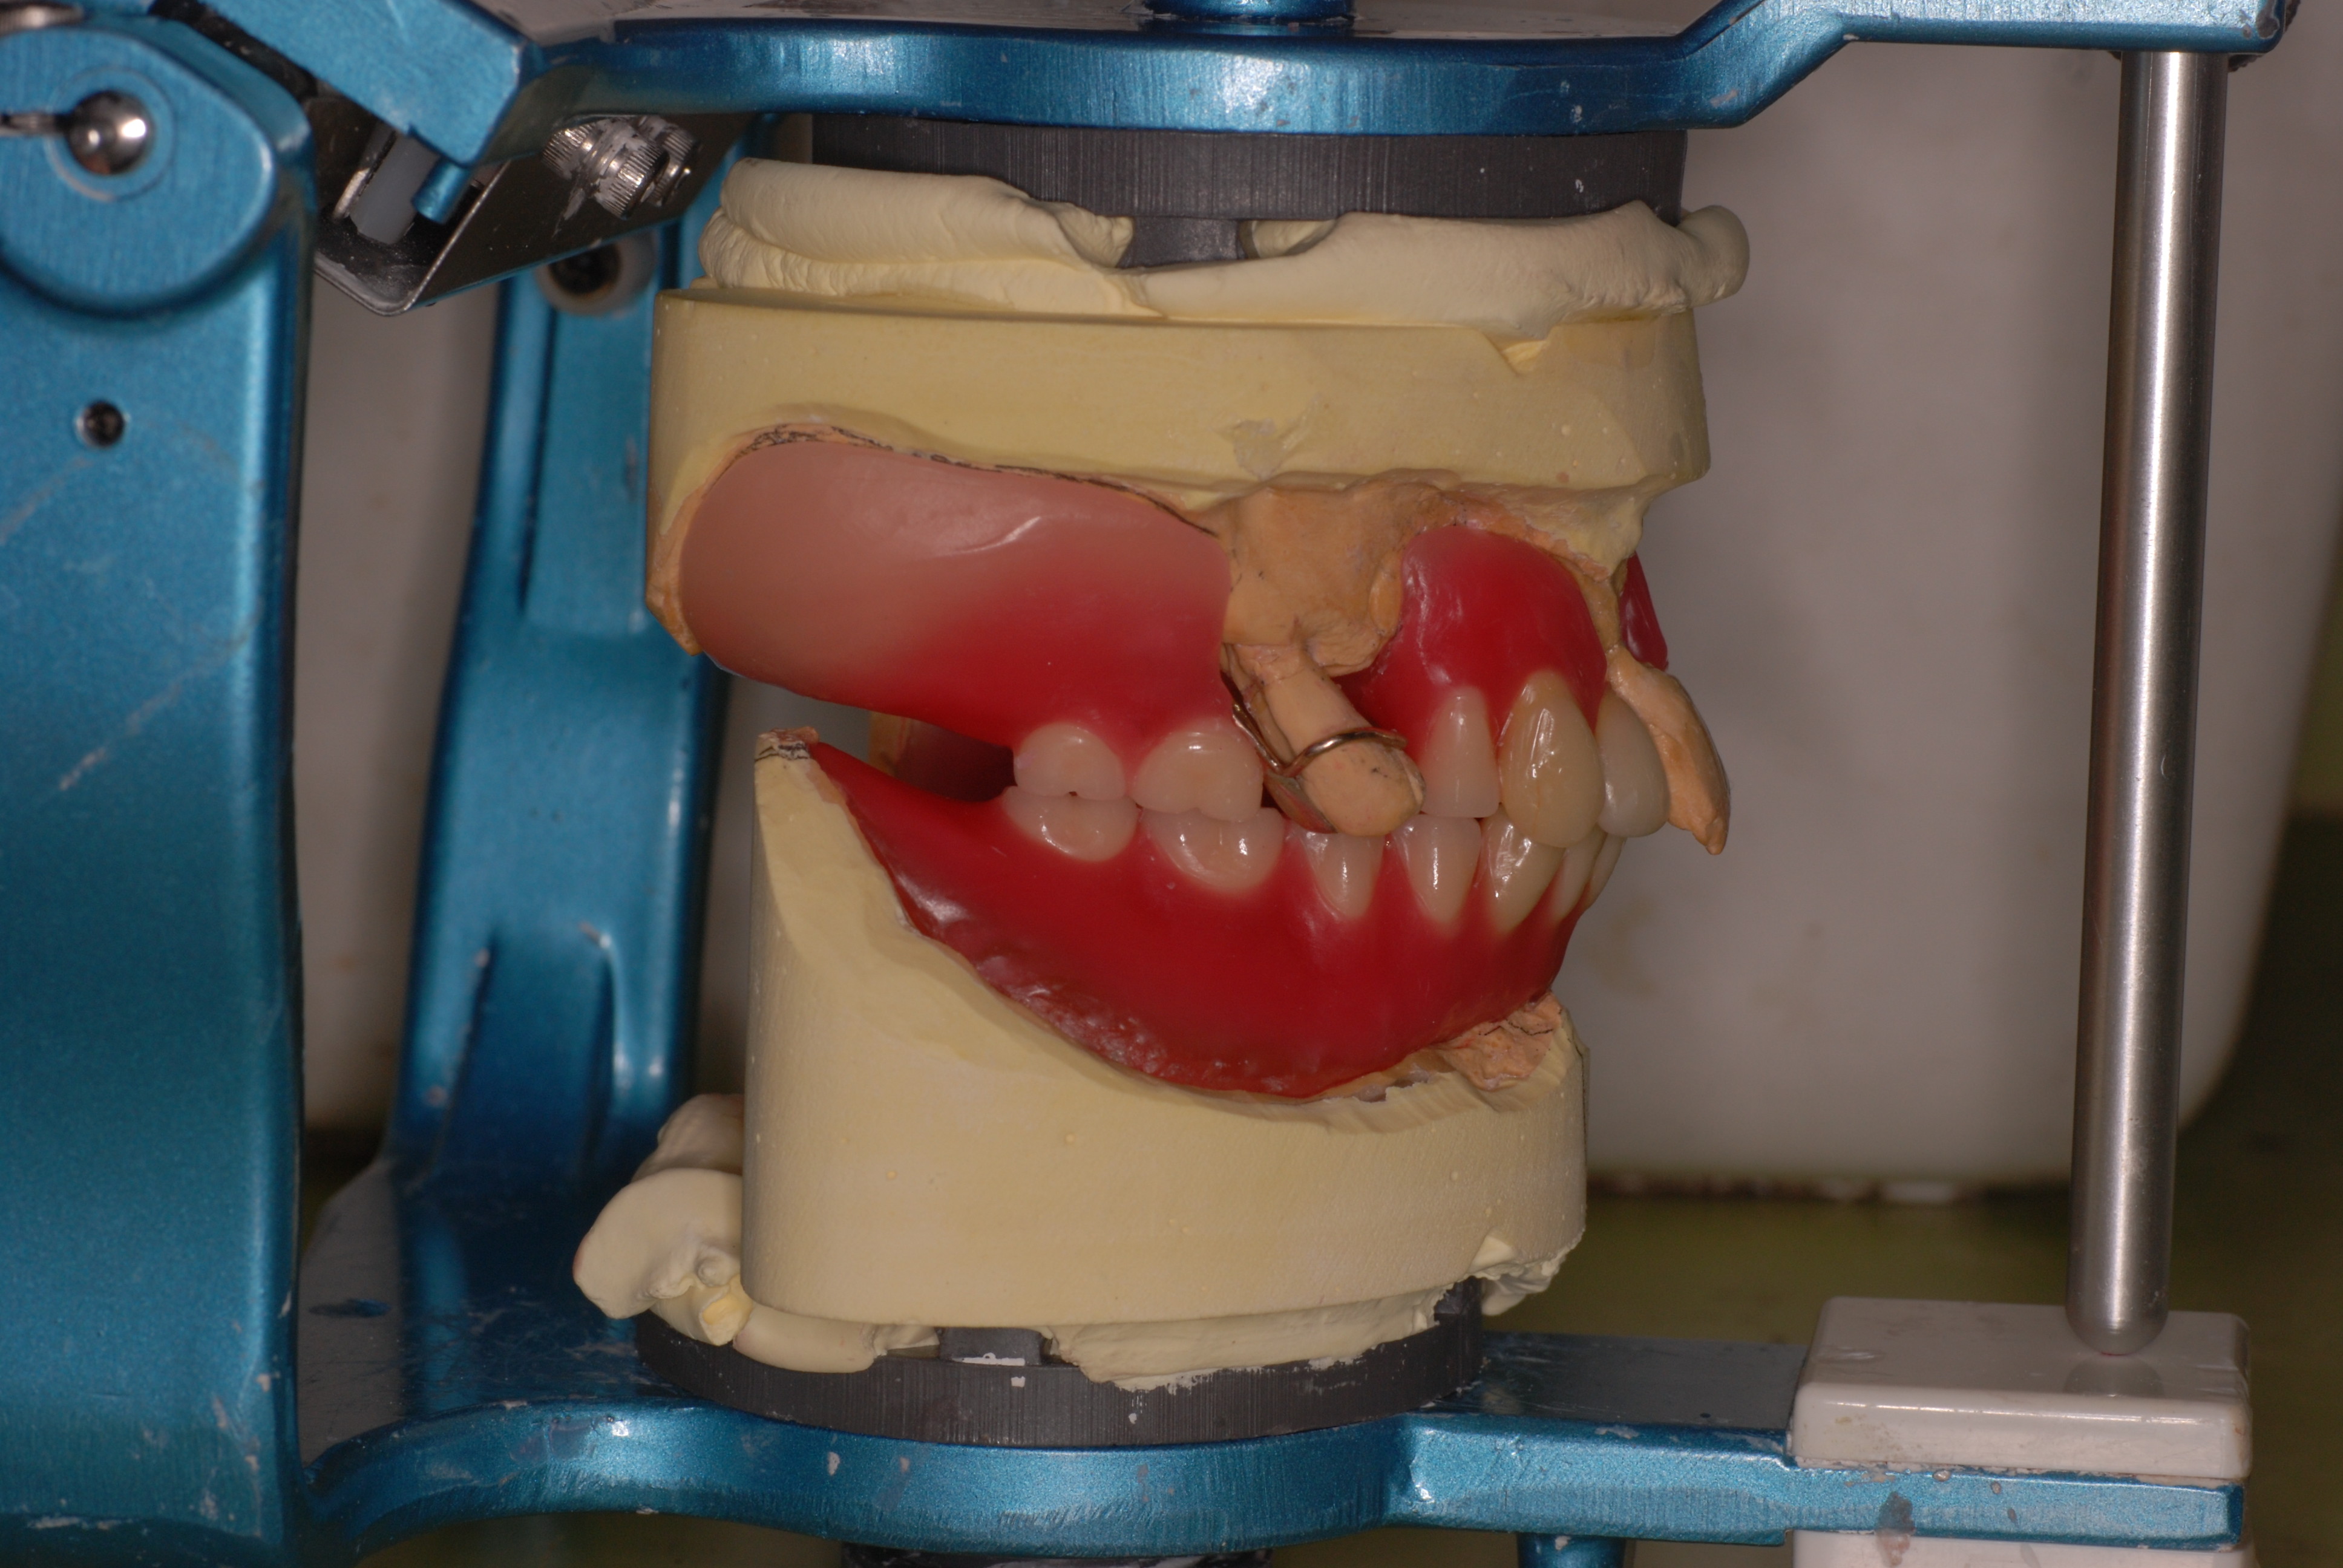

重症の歯周病について,その後

重症の歯周病について、その後

すごい出っ歯になっています。でも噛めています。

とても難しいものでしたが。

DSC_0022DSC_0014